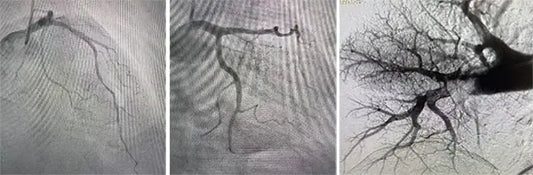

On April 11, 2025, Professor Cai Jun and his team from the Hypertension Center at Beijing Anzhen Hospital successfully performed China’s first ultrasound renal sympathetic denervation (uRDN), marking a historic...